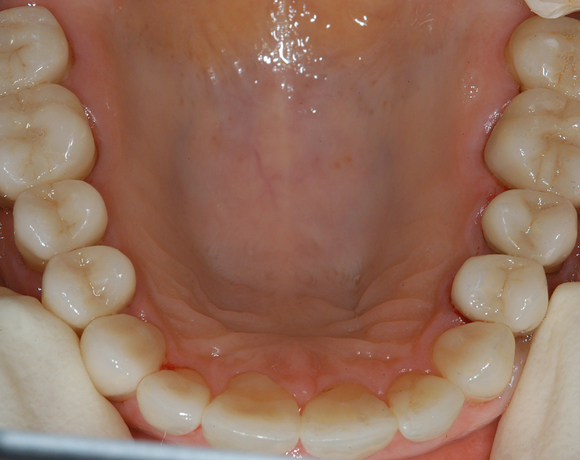

22 Einzelkronen mit Eris for E II

Empress II Presskeramik mit Eris Verblendkeramik bei einer Neuversorgung im Oberkiefer komplett und im Unterkiefer Vollkronen auf den Seitenzähnen.

Ein Projekt aus dem Jahr 2004

Hier wurden der ganze Oberkiefer und die Seitenzähne im Unterkiefer mit neuen Kronen aus Empress 2 und mit Eris Verblendkeramik versorgt.